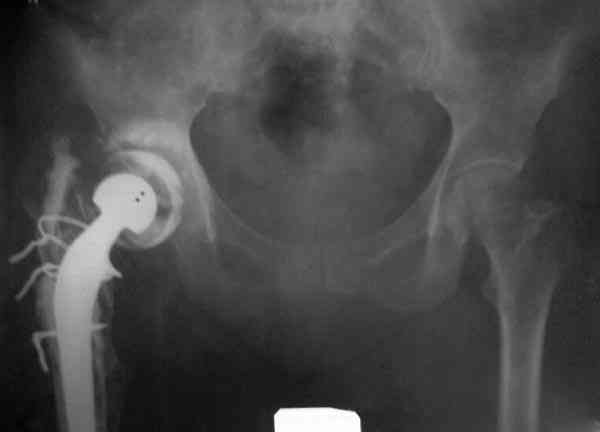

Приглашенный хирург установил ревизионный вариант бедренного компонента без замены ацетабулярного компонента, что осложнилось нагноением и свищами на уровне сустава и средней трети бедра. После двухгодичного безуспешного лечения перевязками и антибиотиками больная обратилась к нам на консультацию.

Для спейсера в бедро использовал старый длинный бедренний компонент меньшего диаметра, облепленный со всех сторон цементом с антибиотиком.

Наглухо ушитая рана с дренажом зажила первично, после чего с больной потерял контакт, и только недавно, через 8 лет я осмотрел её. Она без проблем нагружает на конечность и передвигается с помощью трости. От окончательной операции по реконструкции отказывается, довольная результатом.

Имеются литературные данные, когда спейсер держали не более 6 месяцев, но этот случай бьет все рекорды, может быть для наших людей, обременных финансовыми трудностями, нужна другая шкала оценки сроков нахождения спейсеров.

№3-6 снимки с осложнением

и последние снимки.